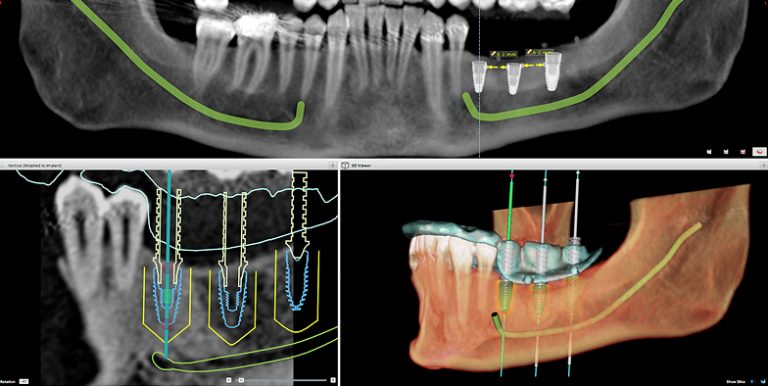

Cada tratamiento es planificado con tecnología 3D y ejecutado con precisión por especialistas con formación internacional y amplia experiencia clínica.

Combinamos tecnología avanzada —como cirugía guiada por ordenador, escáner 3D y planificación digital— con la experiencia de nuestros especialistas en implantología y estética dental. Así logramos rehabilitaciones completas que devuelven no solo la sonrisa, sino también la seguridad y la calidad de vida de cada paciente.